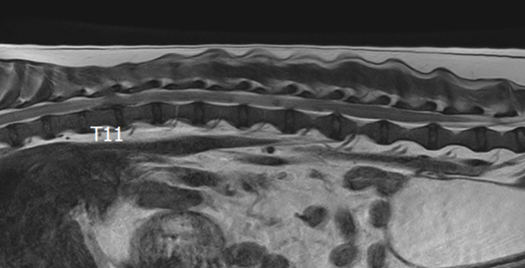

3T MRI

기존 본원에서 이용하던 1.5T 장비와 비교하여 높은 해상도와 빠른 스캔 시간(촬영 부위 당 30분 미만)으로 MR 촬영 시 환자의 마취 부담을 줄일 수 있습니다.

3T MRI는 국내 동물병원에서 최상급 촬영 장비에 해당하며 본동물의료센터의 MRI는 3T MRI 중에서도 하이엔드급 장비(Philips Ingenia)를 사용하고 있습니다.

정상 디스크

급성 추간판 탈출증 환자

02척추 MRI

· 통증, 마비의 원인 진단

· 척추 실질 질환의 진단

· 추간판 탈출증, 척수공동증, 척수연화증 등